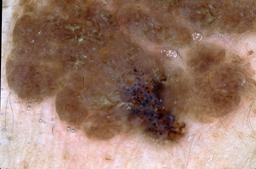

{

"age_approx": 70,

"anatom_site_general": "upper extremity",

"concomitant_biopsy": true,

"dermoscopic_type": "contact non-polarized",

"diagnosis_1": "Benign",

"diagnosis_2": "Benign melanocytic proliferations",

"diagnosis_3": "Nevus",

"diagnosis_4": "Nevus, Combined",

"diagnosis_confirm_type": "histopathology",

"image_type": "dermoscopic",

"lesion_id": "IL_5477327",

"melanocytic": true,

"patient_id": "IP_3514971",

"sex": "female"